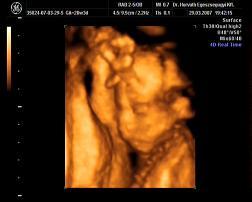

Mi meg megjöttünk az uh-ról, Ákosom nagyon szégyenlősvolt, már ami a kis arcát illeti, mert végig az arca előtt volt mindkétkeze, dörzsölte a szemét....néha profilból el lehetett kapni egy-egy pillanatot, szerintem gyönyörű...már olyan babás! Bezzeg a kukacát, azt mutogatta szorgosan! Meg megmutatta a kezeit, lábait, és hát néha a kis arcát is ki lehetett venni, de szemből teljesen most nem mutatta meg magát. De ami a legfontosabb, minden a legnagyobb rendben Vele, a gerince gyönyörű, gyomortelítődés szépen látható, vesék is szépek, koponya rendben....szóval minden okés, és ez a lényeg. Már 31O gramm a kis Drágám! Nagyon jó volt az egészvizsgálat, csak azt sajnálom, hogy nem sikerült képet készíteni Róla, pedig a doki mindent megtett...deDVD-t kaptunk, majd abból megpróbálok valamit kiügyeskedtetni Apával.

Hagyjatok aludniiiiiiiiiii!!!

Kép

porsika